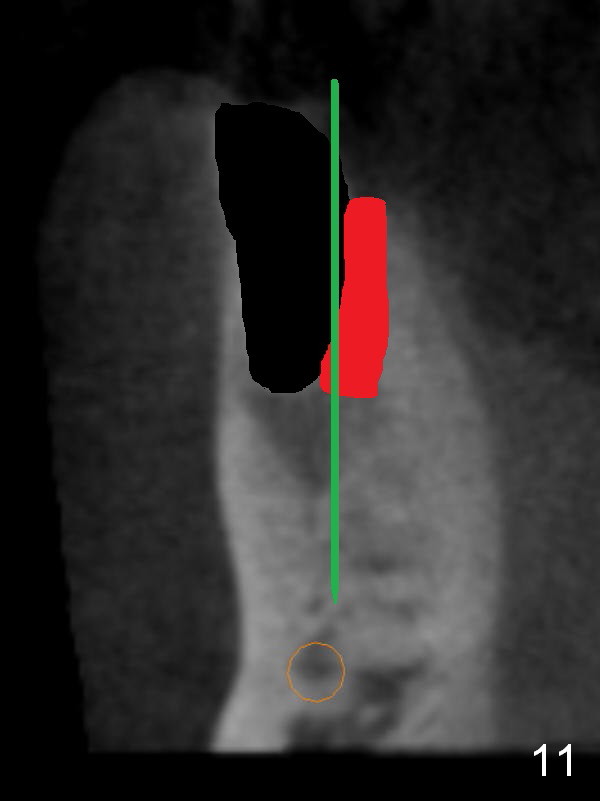

CT sagittal section shows that it is possible to place 4.5x20 mm implant (Fig.6). Axial (Fig.7) and coronal (Fig.9) sections show that the lingual (L) plate is much thicker than the buccal (B) one. To prevent the implant being buccally deviated, a Lindermann bur is used after extraction (black area in Fig.8,10) to remove ~ 1mm bone from the lingual plate (red area in Fig.8,11). A 2 mm pilot drill is placed as lingual as possible (green in Fig.8,11). If the implant (Fig.12) starts to deviate buccally while being placed, remove it from the osteotomy and remove more bone from the lingual plate. Place the implant again and monitor the trajectory tightly.